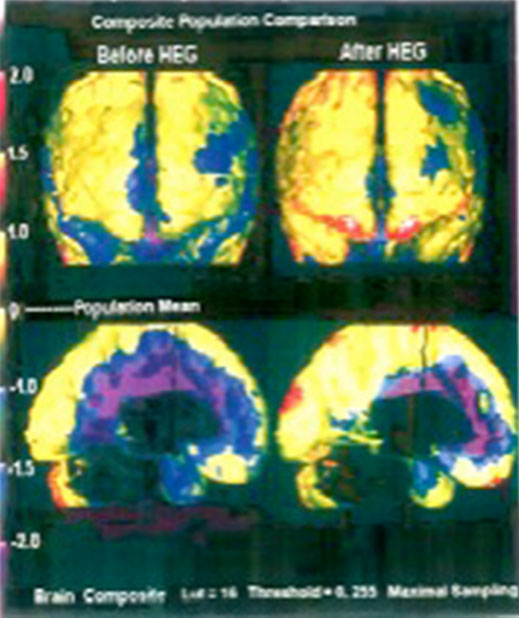

Aufnahmen mit einer Infrarot-Kamera Migräne-Patient. Dunkle Areale signalisieren geringen Blutdurchfluss und scheinen daher „kälter“ als ihre Umgebung.

Linkes Bild: Vor der Behandlung.

Rechtes Bild: nach 5 Sitzungen.